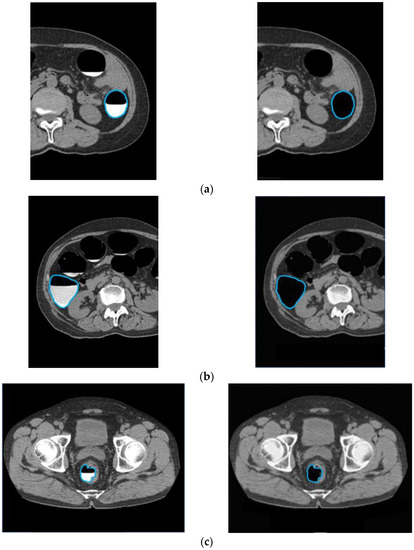

3.1. Cleansing Images Generated Using CycleGAN